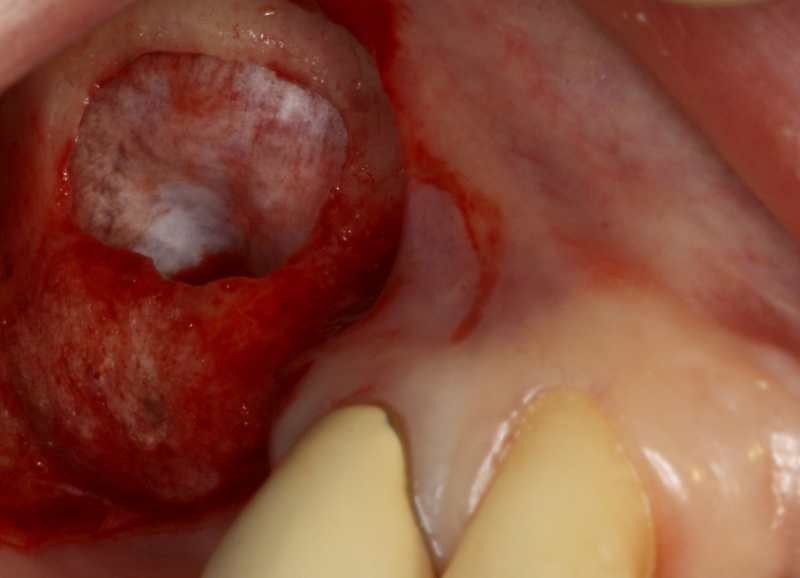

12/20 - Good integration of maxresorb® particles at re-entryGBR with maxresorb® & Jason® membrane - Prof. Dr. Dr. D. Rothamel